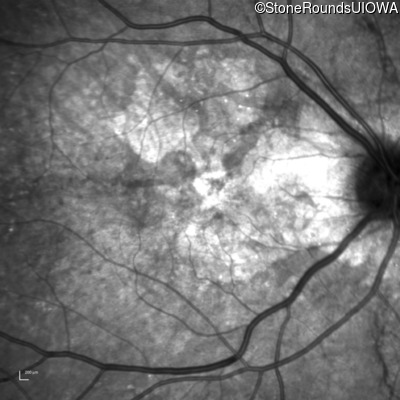

Infrared Fundus Photograph - Left - 20/25 +3

Exemplar